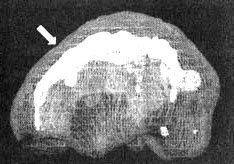

Поясная извилина

Трехмерное изображение — активный мозг

Глубоко в центральной части мозга, вдоль лобных долей, проходит поясная извилина. Это та часть мозга, которая позволяет вам переключать внимание с одного объекта на другой, переключаться с одной мысли на другую, видеть различные варианты решений.

Считается, что она отвечает и за ощущение безопасности.

На мой взгляд, точнее всего функции этой области мозга можно выразить термином «когнитивная гибкость».